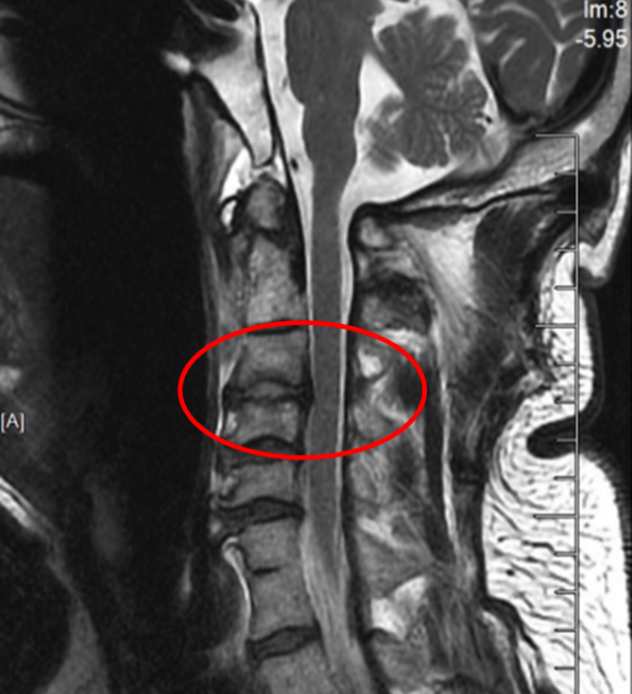

此次手术的成功凝聚了苏大附四院脊柱外科团队多年来在上颈椎领域的深耕细作,是“微创理念”与“智能科技”完美融合的典范。特别是姜为民主任专利研发的新型齿状突螺钉,通过小切口实现了传统开放手术难以企及的精准与安全,兼具微创与稳固的双重优势,为此类疾患治疗带来更佳的方案选择。

图3:骨科机器人